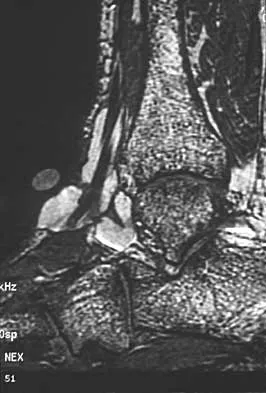

Based on the MRI scan shown in Figure 6, the abnormal signal is seen in what carpal bone?

Explanation